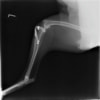

術前左後肢側面像

術後左後肢側面像

術前のTPAは左後肢33.1°右後肢26.8°でしたがTPLO実施により左後肢5.5°右後肢12°に矯正されました。